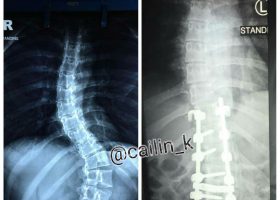

By Jinq En Phee, Swimming World College Intern. Scoliosis is an abnormal lateral curvature of the spin that affects about two percent of the population, including children and adults. While some people